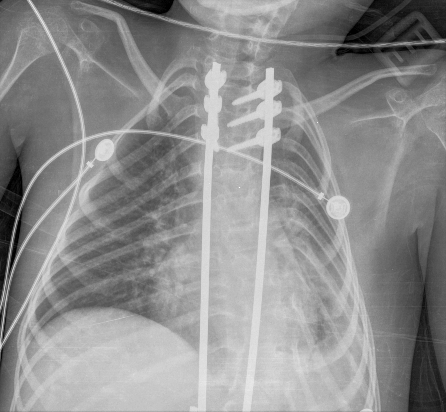

El primer día de internación, se solicitó una radiografía, que evidenció una atelectasia masiva del pulmón izquierdo (Figura 1). En este contexto, se optimizó la THB e interfaz de VNI. Para optimizar la presurización del sistema respiratorio, se cambió la interfaz nasal por una oronasal. El paciente permaneció con su equipo de VNI durante las 24 horas y solo se desconectó para realizar THB. Se monitorearon los signos vitales con el objetivo de mantener una saturación ≥94 % con la menor FiO2 posible. Como parte del plan de THB, se programó ventilación percusiva intrapulmonar (VPI) y CA dos veces al día durante cinco días consecutivos. Se utilizó un equipo de VPI The Impulsator® de Percussionaire con circuitos Phasitron®. Se emplearon 10 minutos en modo easy para favorecer la movilización de secreciones más distales y 10 minutos en modo hard para garantizar el reclutamiento alveolar. Se utilizó una relación I/E de 1:1 o 3:1, según tolerancia, con un rango de presión de la vía aérea entre 10-30 cmH2O y una presión de trabajo de 2-4 bares. Se continuó con CA, con una presión de insuflación de +30 cmH2O y una presión de exuflación de -40 cmH2O, junto con asistencia manual de la tos, con el objetivo de movilizar secreciones de vías aéreas proximales. En el segundo día, ante la ausencia de mejoría, se optimizó el equipo de soporte ventilatorio cambiando la VNI domiciliaria por un equipo de soporte vital. Se colocó un Trilogy 202 (Respironics®) en modalidad binivel, con monorama a fuga, en modo asistido controlado por presión, con humidificación activa y una interfaz facial total. En el tercer día, no se implementaron cambios en la programación de la VNI, y se continuó con la misma THB. En el cuarto día, se interconsultó al servicio de endoscopía respiratoria, quienes otorgaron un turno a la brevedad para realizar una fibrobroncoscopía con intubación e instilación de alfa dornasa, junto con VPI en línea con ventilación mecánica, como método invasivo de resolución de atelectasias. En el quinto día, se realizó una nueva radiografía, que mostró una reducción significativa del área atelectásica (Figura 2), lo cual se objetivó con mejoría clínica. Esto permitió descender las presiones, y se volvió a su programación habitual. Asimismo, se finalizó el uso de la VPI y se continuó únicamente con CA y asistencia manual de la tos. Después de 24 horas, el paciente estaba llevando a cabo dos períodos de 3 horas de desconexión de la VNI a aire ambiente. A las 48 horas, se logró la desvinculación de la VNI diurna, con reconexión nocturna a su equipo domiciliario e interfaz nasal. En el séptimo día, se confirmó la resolución de la atelectasia en la radiografía (Figura 3), quedando suspendida la intervención de endoscopía respiratoria. En el octavo día, se le otorgó egreso hospitalario. En la Figura 4, se resume la evolución del paciente.